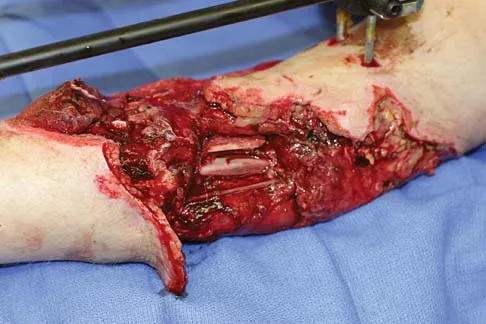

A 25-year-old man shot himself at the base of the right index finger while cleaning his handgun. Examination reveals that the finger is cool and cyanotic. A clinical photograph and radiograph are shown in Figures 44a and 44b. What is the recommended treatment?

Explanation

The gunshot wound has caused injury to multiple systems: bone, vascular, skin, and tendon; therefore, the treatment of choice is amputation. An immediate ray amputation allows for a more rapid return to activities and less time off work. Peimer CA, Wheeler DR, Barrett A, et al: Hand function following single ray amputation. J Hand Surg Am 1999;24:1245-1248.